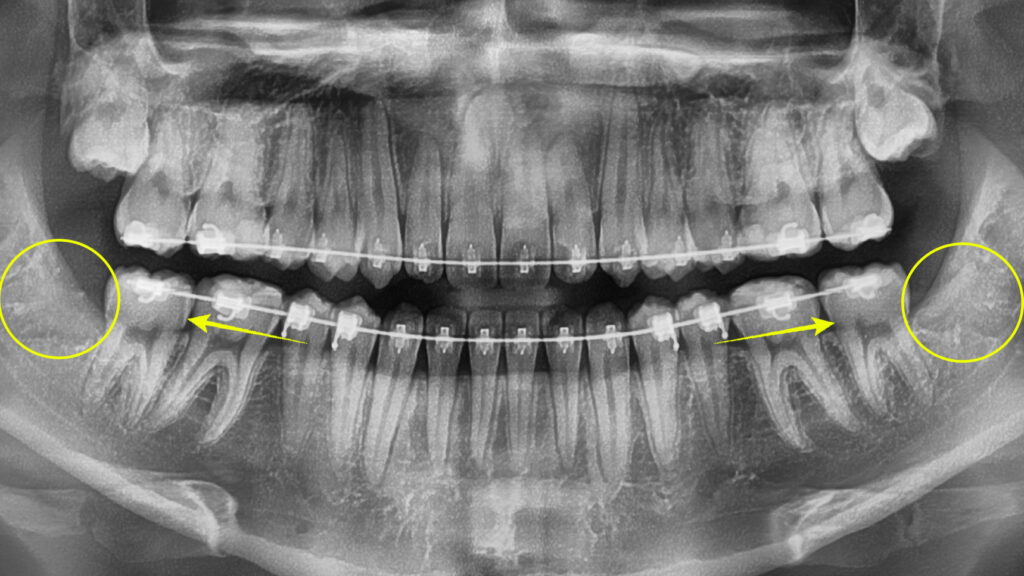

치료의 핵심은 비발치 교정을 통해 교합 관계를 개선하는 것이며, 골격성 3급 부정교합의 교정치료는 단순히 치아를 움직이는 것 이상의 의미를 갖습니다.

골격적 부조화가 있는 상황에서 치아의 위치를 조정하여 최적의 기능과 심미성을 달성해야 하므로, 치료 과정 전반에 걸쳐 세밀한 관찰과 지속적인 조정이 필요합니다.

또한 하악 사랑니 발치도 치료 계획에 포함됩니다. 사랑니는 아랫니를 후방으로 이동시키는 데 물리적 장애물이 될 수 있으며, 특히 3급 부정교합 환자에서는 하악 전치의 후방 이동을 위한 공간 확보가 매우 중요하기 때문입니다.

특히 앞니 반대교합의 해소 과정에서는 상하악 전치 간의 관계 변화를 단계별로 모니터링합니다.